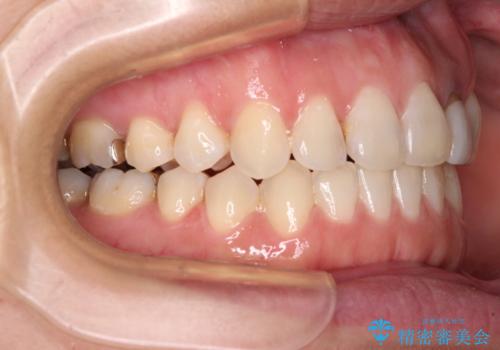

開咬と変色した前歯 インビザライン矯正とオールセラミッククラウン治療

- 前歯の開咬と失活により変色した前歯を気にして来院された患者様です。

開咬の治療は、前歯を閉じるように引っ張り出すよりも、上下臼歯を圧下(骨内にめり込ませる)させることで進める方が長期的に安定した歯列を維持できます。

インビザラインは臼歯の圧下を効果的に行えるため、インビザラインを用いて矯正治療を行うこととしました。

矯正治療が概ね終了した時点で前歯をオールセラミッククラウンにて補綴治療を行い、その後インビザラインにて細かい部分を仕上げていくことしました。